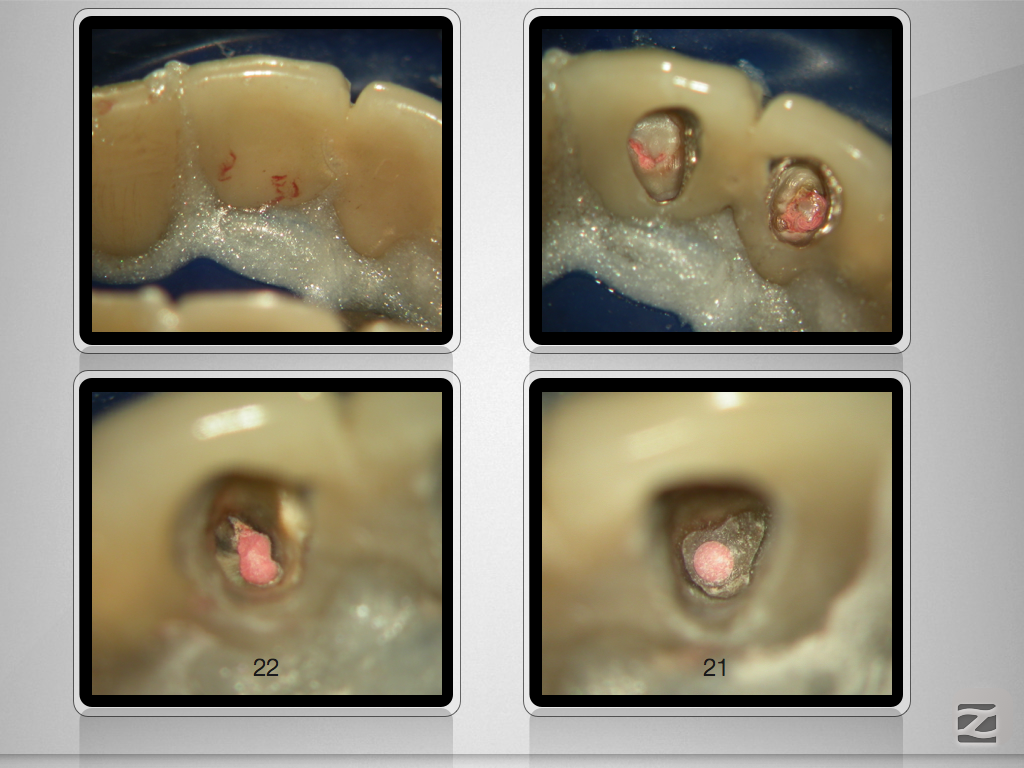

Saving Hopeless Teeth – Zustand nach WSR